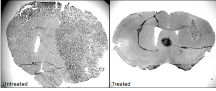

glioblastoma.png